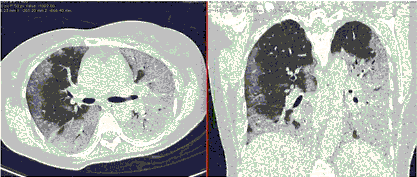

2. Наличие клинических проявлений, указанных в п. 1, в сочетании с характерными изменениями в легких по данным компьютерной томографии (КТ) (см. Приложение 1 настоящих рекомендаций) вне зависимости от результатов однократного лабораторного исследования на наличие РНК SARS-CoV-2 и эпидемиологического анамнеза.

- Изменения в легких при КТ (рентгенографии), типичные для вирусного поражения (объем поражения значительный или субтотальный; КТ 3-4)

- Изменения в легких при КТ (рентгенографии), типичные для вирусного поражения критической степени (объем поражения значительный или субтотальный; КТ 4) или картина ОРДС.

КТ имеет высокую чувствительность в выявлении изменений в легких, характерных для COVID-19. Применение КТ целесообразно для первичной оценки состояния ОГК у пациентов с тяжелыми прогрессирующими формами заболевания, а также для дифференциальной диагностики выявленных изменений и оценки динамики процесса. КТ позволяет выявить характерные изменения в легких у пациентов с COVID-19 еще до появления положительных лабораторных тестов на инфекцию с помощью МАНК. В то же время, КТ выявляет изменения легких у значительного числа пациентов с бессимптомной и легкой формами заболевания, которым не требуется госпитализация. Результаты КТ в этих случаях не влияют на тактику лечения и прогноз заболевания при наличии лабораторного подтверждения COVID-19. Поэтому массовое применение КТ для скрининга асимптомных и легких форм болезни не рекомендуется.